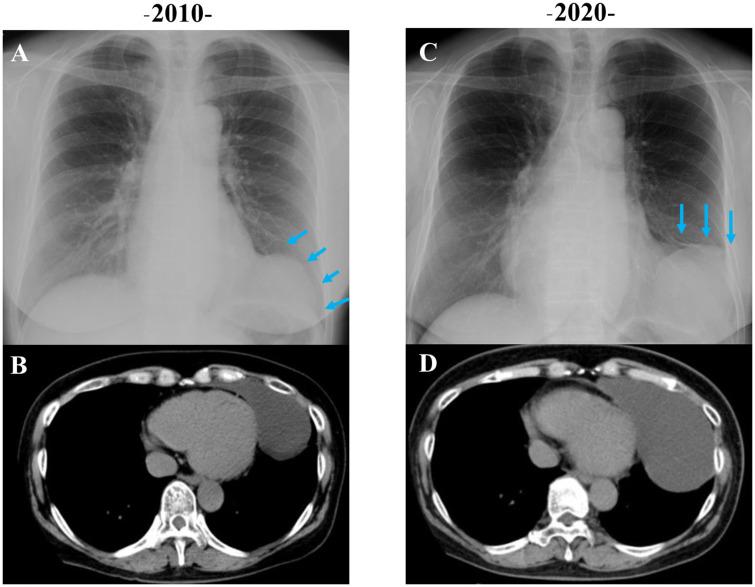

We report a case of a 59-year-old female with a gradually increasing pericardial cyst, first noted 10 years prior as an abnormal cardiac silhouette on routine chest radiography. Further evaluation confirmed the presence of a pericardial cyst compressing the left ventricle with new-onset atrial fibrillation. The patient underwent successful thoracoscopic excision of the pericardial cyst under general anaesthesia. The patient's post-operative course was uneventful, and she was ultimately discharged in stable condition.

我们报告一例59岁女性,心包囊肿逐渐增大,10年前在常规胸部X线检查时首次发现心脏轮廓异常。进一步评估证实存在心包囊肿压迫左心室并伴有新发房颤。患者在全身麻醉下成功接受了胸腔镜下心包囊肿切除术。患者术后恢复顺利,最终病情稳定出院。